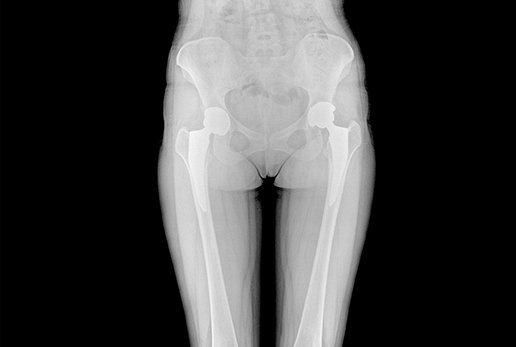

● 采用自主研發(fā)脈沖技術(shù),大尺寸動態(tài)平板,可實現(xiàn)動、靜態(tài)攝影模式無感切換,呈現(xiàn)更優(yōu)質(zhì)的圖像,為臨床醫(yī)生提供診斷依據(jù)。

● 集攝影、透視、造影等多功能為一體

● 核心優(yōu)勢: 大功率 動態(tài)平板 高清攝影 快速成像 透視造影 高清點片